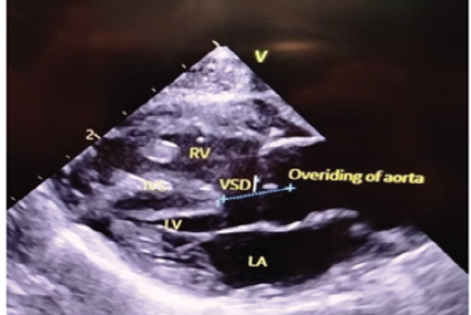

Abstract: Pentalogy of Fallot is a rare form of congenital cyanotic heart disease with a prevalence of 3/10,000 live births characterized by an association of Tetralogy of Fallot with Atrial Septal Defect. Pentalogy of Fallot with anorectal malformation is also a rare combination. Here we describe one of the rare case reports of a full-term, 38 weeks, female baby diagnosed with pentalogy of Fallot with imperforate anus and rectovaginal fistula at a tertiary care hospital. Pentalogy of Fallot combined with an imperforate anus and rectovaginal fistula is an exceptionally rare and complex congenital condition. The co- existence of these anomalies emphasizes the need for thorough prenatal and postnatal evaluation for early detection and management.